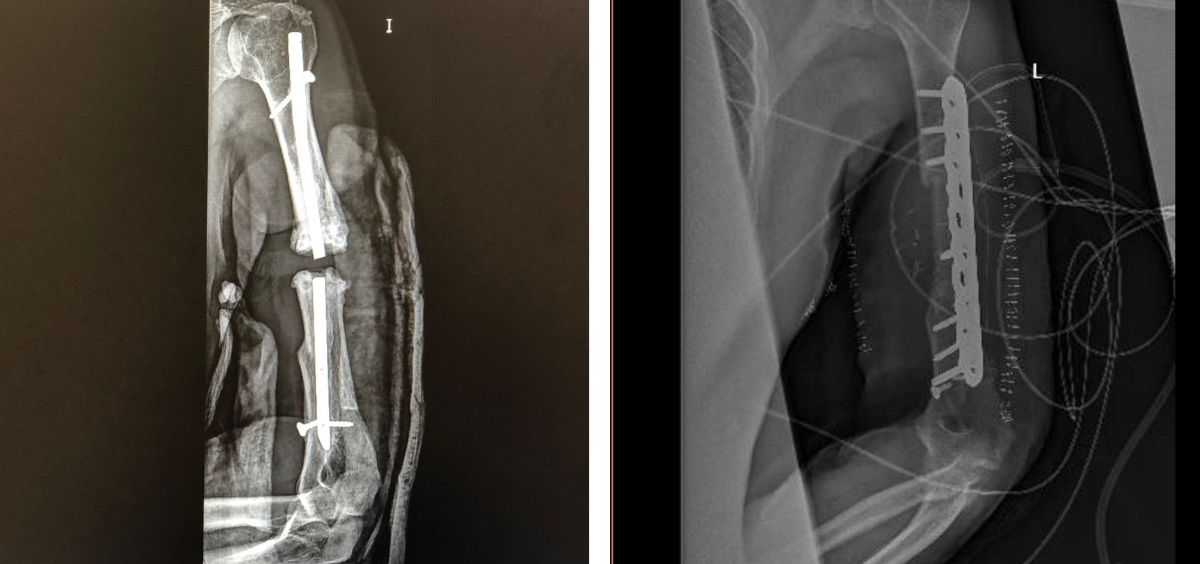

Gracias a todo ello, el Hospital Universitario General de Villalba pudo realizar recientemente una innovadora cirugía de reconstrucción, utilizando el modelo 3D y las guías de corte quirúrgico impresas en 3D, específicas y adaptadas a la anatomía del paciente, en un varón con fractura muy compleja del húmero como consecuencia de un accidente de tráfico hace diez años.

El paciente se había sometido a varias intervenciones en distintos centros hospitalarios, sin conseguir consolidación de los fragmentos óseos, y actualmente el hueso presentaba "pseudoartrosis" por falta de flujo sanguíneo, requiriendo resecar la parte del húmero afecto y aportar nuevo hueso sano. En este caso, el equipo quirúrgico liderado por el Dr. Alfonso Prada, especialista del el Servicio de Cirugía Ortopédica y Traumatología del hospital villalbino, en colaboración con el Servicio de Cirugía Oral y Maxilofacial de este centro y de los citados valdemoreño y mostolense, planteó un abordaje poco convencional para reconstruir el hueso.

"Realizamos un trasplante utilizando el peroné del propio paciente para adaptarlo al defecto previamente planificado de hueso humeral"; explica la Dra. Lorena Pingarrón, jefe del Servicio de Cirugía Maxilofacial, recordando la cirugía multidisciplinar en la que, junto a los doctores Paula Barba y Santos Crespo, especialistas del mismo servicio, "se adaptó a las necesidades que el Dr. Prada transmitió en su paciente para obtener, en conjunto, el mejor resultado funcional".

Gracias a la planificación milimétrica del defecto, el equipo de Planificación Quirúrgica 3D pudo diseñar las guías de corte del peroné y del húmero y realizar un estudio tridimensional junto con los cirujanos para acoplar el trasplante de hueso de la pierna al brazo. "La cirugía transcurrió sin complicaciones, con reducción considerable del tiempo quirúrgico con respecto a una intervención sin planificación tridimensional", concluyen los doctores Prada y Pingarrón, recordando que el paciente fue dado de alta a los 4 días de la operación.